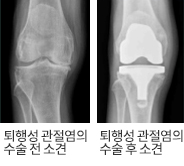

퇴행성, 류마티스성 관절염이나 외상 후에 발생한 관절염으로 무릎의 연골이 닳아서 통증이 심하고 움직임에 제한이 있으며 다리가 휜 경우에 마모된 여놀을 절제해 내고 인공관절을 삽입합니다. 수술 후 2주면 퇴원이 가능하고 3개월 정도며 지팡이나 목발 없이 자유로운 활동이 가능합니다.

- 엑스레이 소견